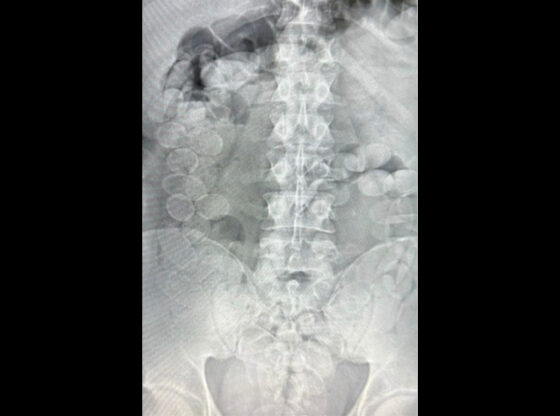

Ante la gravedad de la situación, GNA informó lo sucedido a la Sede Fiscal Descentralizada Rafaela, que ordenó el inmediato traslado e internación de los involucrados al Hospital de Ceres, donde los estudios radiográficos confirmaron la presencia de cuerpos extraños compatibles con cápsulas en sus organismos.

Finalmente, expulsaron un total de 185 cápsulas de cocaína: 93 envoltorios con 1.239 gramos extraídos de uno de ellos y 92 envoltorios con 1.212,3 gramos correspondientes a otro.